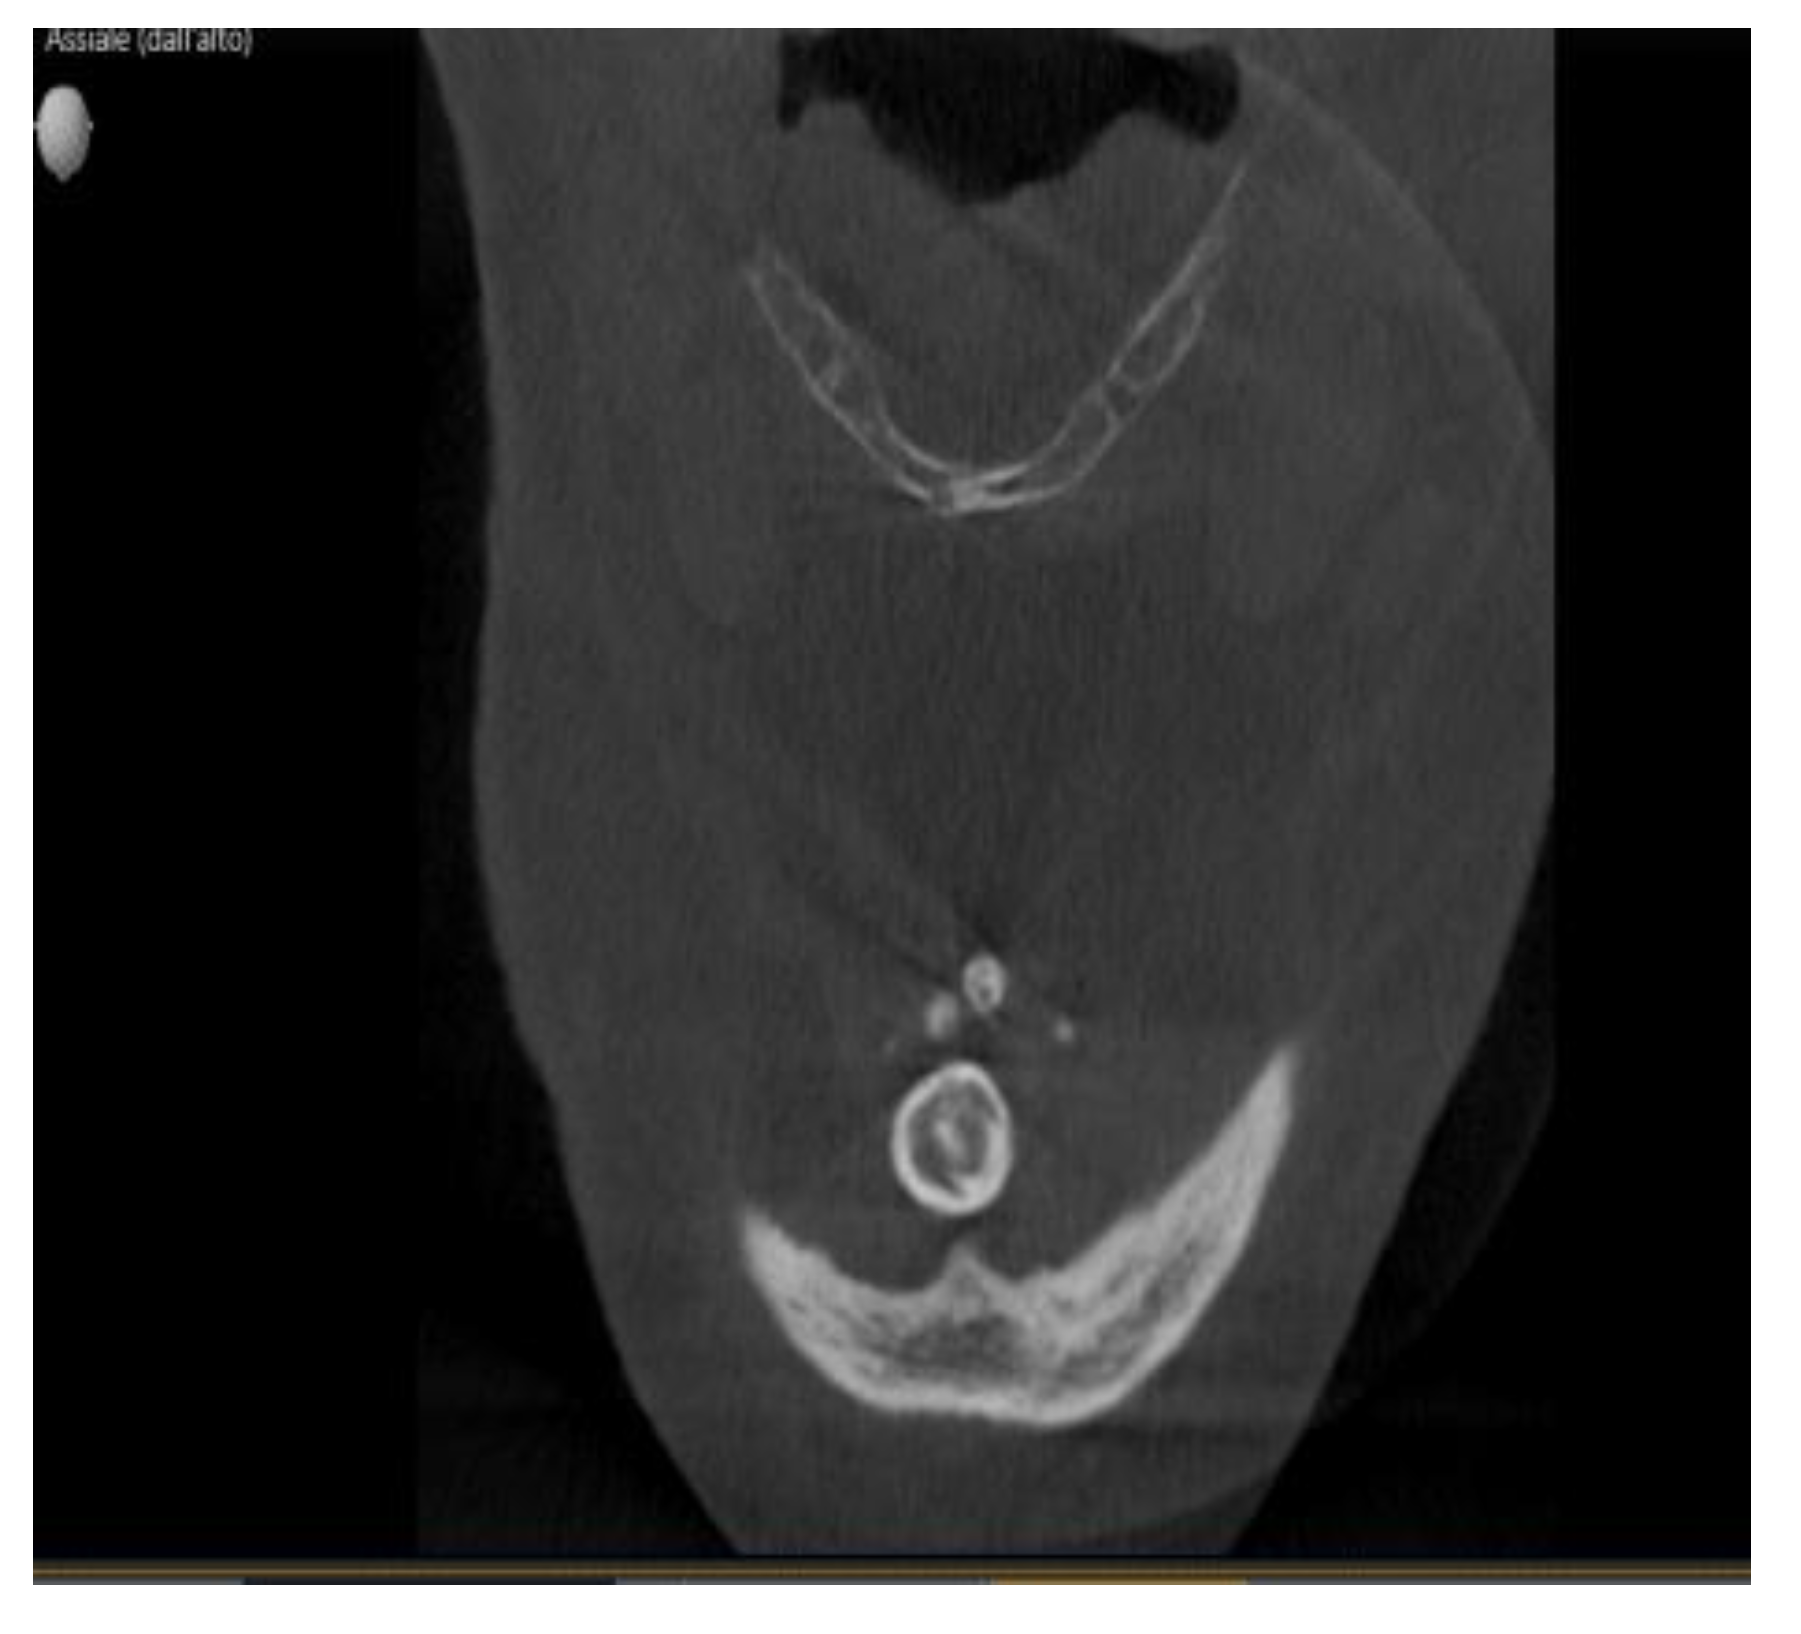

Enigmatic Formations Found in Routine Orthopantomography (OPG) Examinations: A Case Report

2. Case Presentation